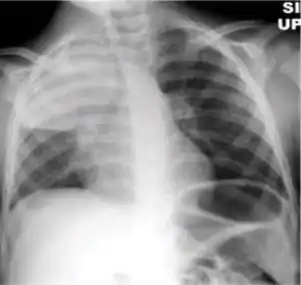

1. Infiltrate or consolidation - Opacification of airspaces within the lung parenchyma. Consolidation or infiltrate can be dense or patchy and might have irregular, ill-defined, or hazy borders.

Dense homogenous opacity in right, middle and lower lobe of primary pulmonary TB.